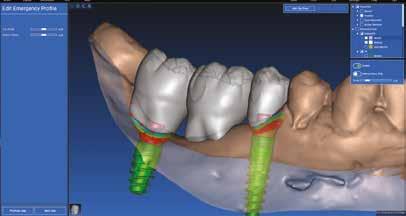

BTI range is one of the most complete in the market, covering technologies, concepts and products that can respond to all the needs of the dental practice, from surgical planning using the BTI Scan4 software to surgery, by means of the versatile system of implants and, of course, the restoration through prosthetic components with a great precision in the machining and CAD CAM systems.

Thanks to recent advances in research, the BTI system of implants has a surface of unique characteristics: topography of triple roughness modified with free calcium ions, which enables the adhesion and activation of platelets instantaneously during the moment

Geass offer also includes complete solutions for digital dentistry: digital impression taking, computer assisted surgery and CAD-CAM personalized prosthesis.